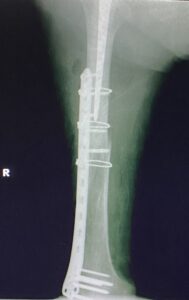

- Περιπροθετικό κάταγμα λίγο πιο κεντρικά από το πέρας του εμφυτεύματος του γόνατος

- Ευθυγράμμιση του οστού και η οστεοσύνθεση με ειδική πλάκα τιτανίου και κλειδούμενους κοχλίες.